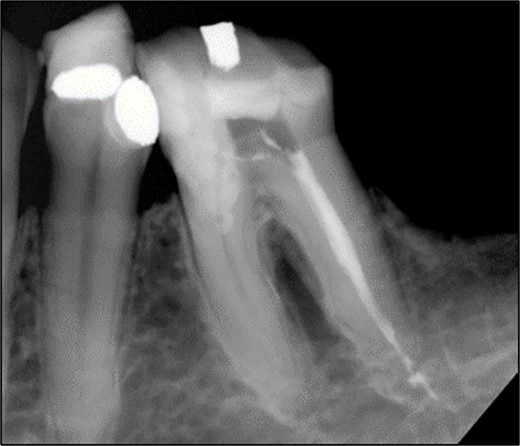

After removal of the existing restoration and caries, the cavity margin on the mesial side was noted to be 1 mm subgingival, with a mid-palatal margin extending to the root surface. Non-surgical root canal treatment was performed under local anesthesia and rubber dam isolation. Only the DB and DL canals were cleaned and shaped, and obturation was completed using ProTaper Gold gutta-percha with AH Plus sealer (Dentsply, Konstanz, Germany) (Fig. 8).

Periapical radiograph of tooth 36 with obturation on DB and DL canal. Sealer extrusion noted.